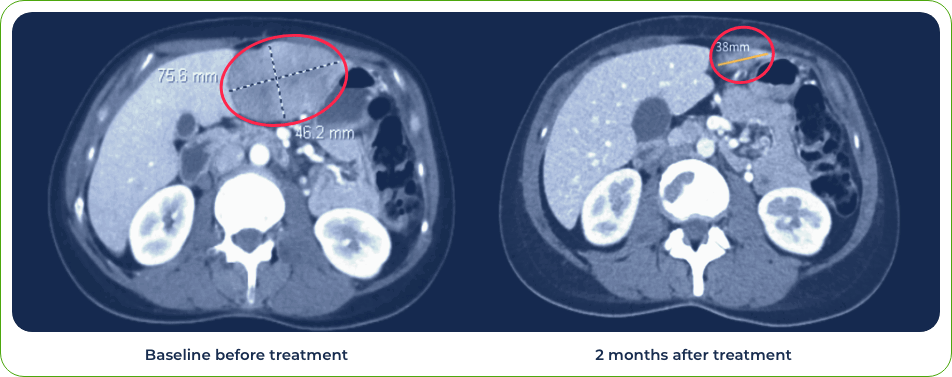

Diagnosis:

Stage IV lung adenosquamous carcinoma

Sites of metastases:

Adrenal glands and brain